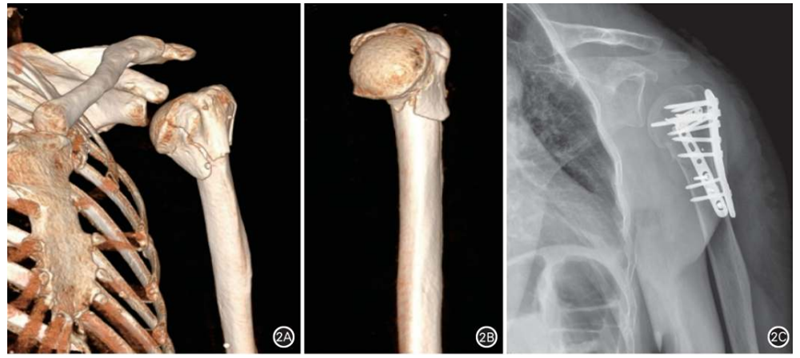

外侧钢板固定后,附加额外钢板内固定技术称为肱骨近端骨折双钢板固定(图2)。肱骨近端骨折双钢板固定提供了更强的内侧支撑并降低术后复位丢失率。适应证:肱骨近端四部分骨折伴肱骨距粉碎骨折,不适宜进行人工肩关节置换的年轻患者;粉碎性内侧距骨折难以复位或发现复位无法维持者等。一般选择微型钢板作为辅助固定钢板,辅助钢板固定的部位可以选择内侧、前侧或后侧,各有利弊。前侧辅助固定钢板操作简单,以结节间沟为复位标准,通过固定肱骨头与骨干,桥接固定肱骨距粉碎骨折;无须剥离过多软组织,有利于保留残存的肱骨头血供。内侧辅助钢板有直接支撑内侧距的作用,但是钢板近端需要固定至肱骨解剖颈下缘,术后存在钢板与肱骨头撞击的可能;;时内侧入路容易损伤腋神经及旋肱前动脉。后侧辅助钢板可以起到后方支撑作用,纠正肱骨近端骨折伴发的内翻和后倾移位,但是容易挫伤旋肱后动脉及损伤肩袖,影响术后外旋活动恢复。

图2 肱骨近端骨折双钢板固定。 A、B. 肱骨近端三部分骨折,内侧距粉碎;C. 附加前侧钢板固定术后 6个月,肱骨内侧距骨性愈合